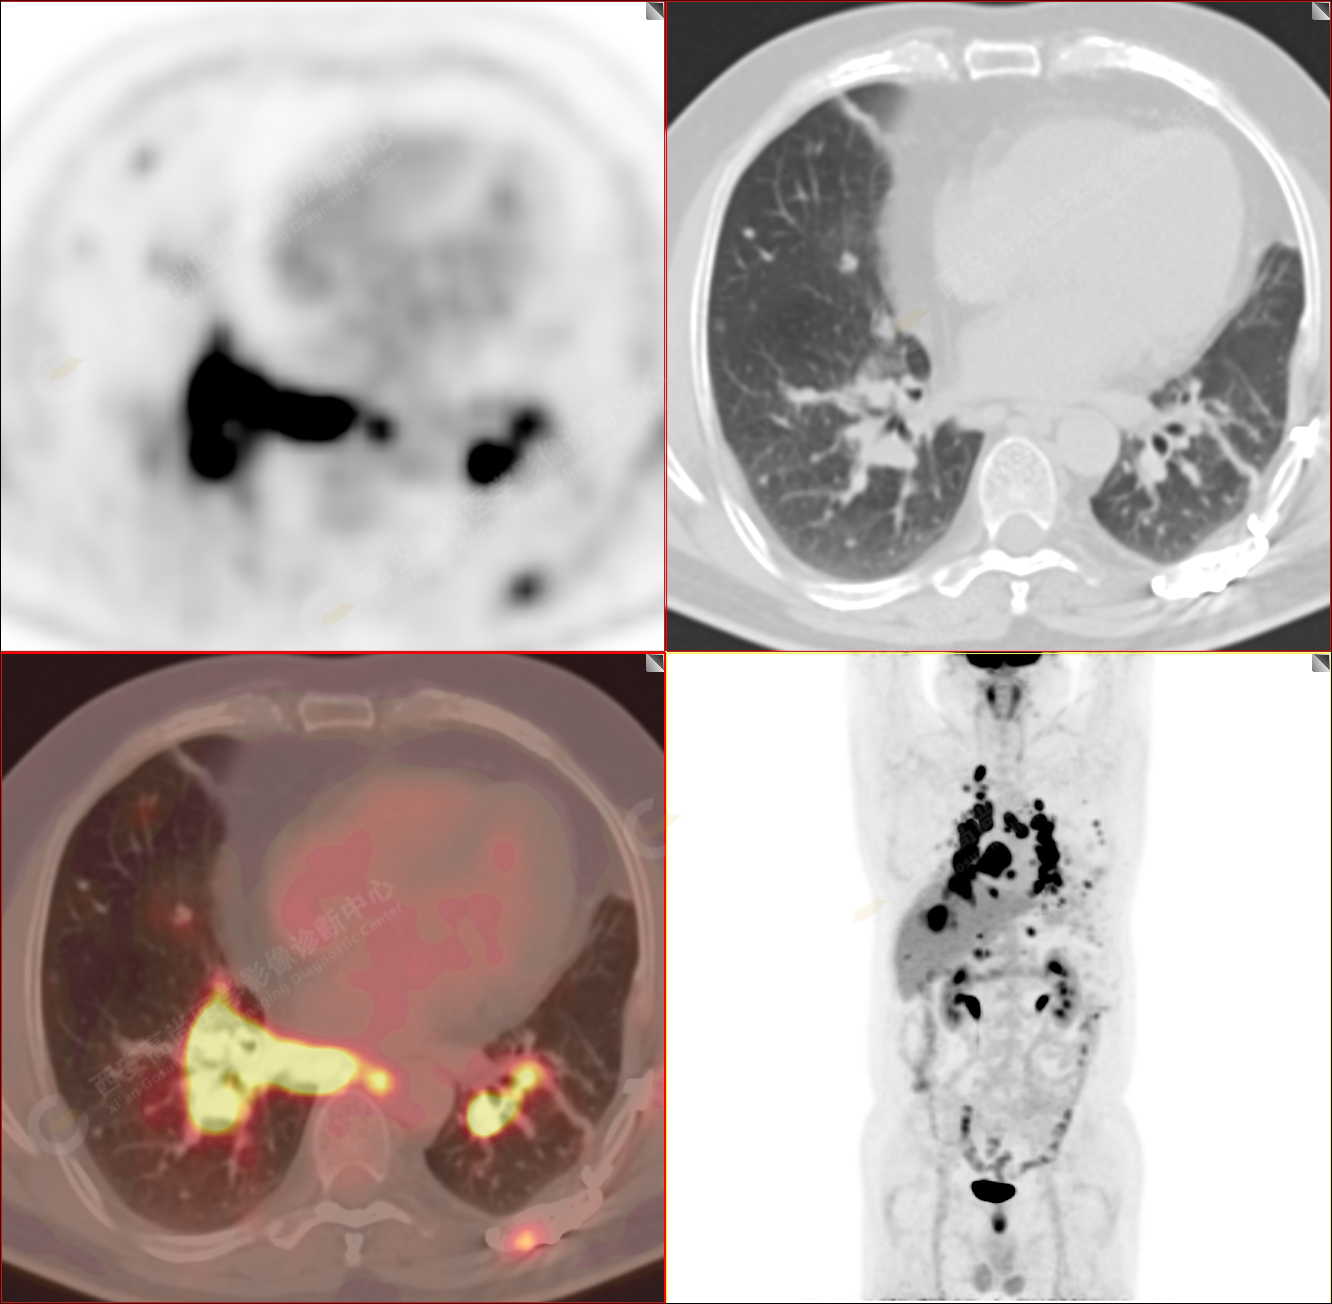

PET/CT圖像